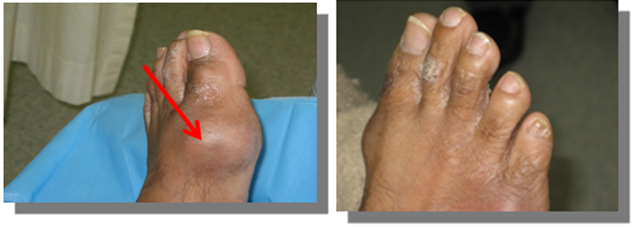

Hands (Figure 1)

Figure 1 Inflamed dorsum of the right hand, skin redness, swelling, and tenderness. Multiple swellings on left hand.

Elbow (Figure 2)

Figure 2 Left elbow had swelling, redness, tenderness, and restriction of movements. Right Elbow had big tophi, soft, rubbery with overlying chalky cheesy material.